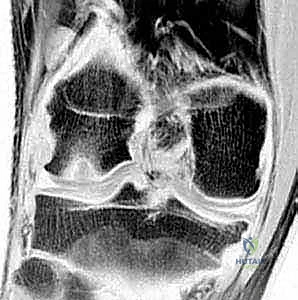

- الأشعة السينية (X-Rays): تُعد الخطوة الأولى لاستبعاد الكسور وتقييم الهيكل العظمي العام، وغالباً ما تُظهر الآفة في المراحل المتقدمة.

- التصوير بالرنين المغناطيسي (MRI): هو "المعيار الذهبي" للتشخيص. بفضل خبرة الدكتور هطيف العميقة، يتم تحليل صور الرنين لتقييم صحة الغضروف، مدى انفصال القطعة العظمية، وحالة الأربطة المحيطة. الرنين يحدد ما إذا كانت الآفة مستقرة (يمكن علاجها بدون جراحة) أو غير مستقرة (تتطلب تدخلاً جراحياً).

- الأشعة المقطعية (CT Scan): قد تُطلب في حالات خاصة لتحديد حجم العظم المفقود بدقة ثلاثية الأبعاد قبل التخطيط للجراحة.